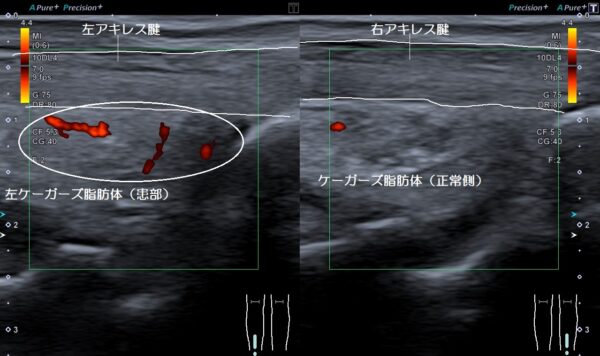

超音波画像観察を行うと左アキレス腱の深部にあるケーガーズ(Kagers)脂肪体に損傷による炎症が発生していました(画像、丸の中の赤色の箇所)。

ケーガーズ脂肪体は、アキレス腱や脂肪体の深部にある足指と足首を曲げる筋肉との摩擦を軽減し、足指と足首の動きをスムーズにする役目があります。

しかし、運動や日常生活での負担が掛かり過ぎると、アキレス腱と脂肪体が硬くなって摩擦が生じ、それぞれの組織が擦り切れるなどの損傷が発生して痛みの原因になります。